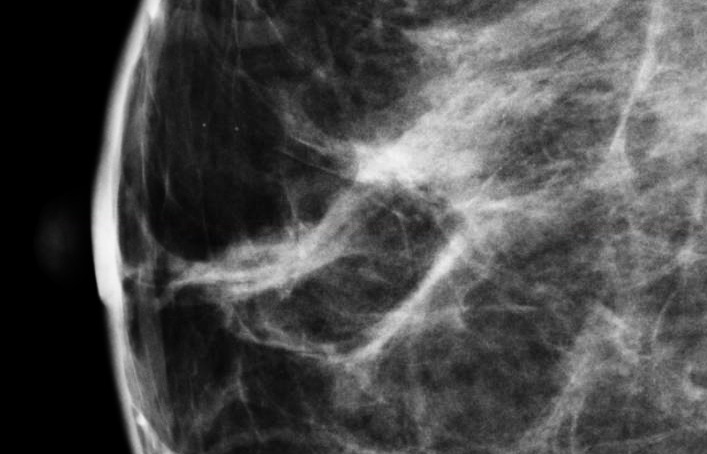

Currently, mammography systems generate a mean glandular dose (MGD) based on an assumption of a homogeneous mixture of fat and fibroglandular tissue in standard proportions.

The first study, “Patient Specific Average Glandular Dose in Mammography,” demonstrated the differences in radiation dose estimation when researchers adjusted the estimation according to the actual volumetric breast density. According to Vikas Patel, M.D., from Upstate Medical Physics (a Landauer Medical Physics partner), the results showed that accounting for the patient-specific breast composition led to estimated radiation doses which were significantly higher than given out by the mammography machines. “Our initial results suggest that current dose estimations may underestimate the actual patient MGD significantly as they do not account for the specific breast tissue composition. Patient-specific dose estimates may give a better indication of the actual dose delivered, and therefore the risk to the patient.”

The second study, “Retrospective Determination of Personalized Mean Glandular Dose Coefficients for Conventional Mammography Using Heterogeneously-layered Breast Models,” by Mariela Porras-Chaverri, department of medical physics, University of Wisconsin-Madison, took the personalization one stage further by not only using the patient-specific volumetric breast density, but also considering how the tissue might be dispersed within the breast. “The glandular and adipose breast tissues are distributed heterogeneously within the breast. Depending on the individual distribution with respect to the beam entrance surface, the mean dose delivered to the glandular tissue may be higher or lower than estimated by the current methods. Our ongoing study aims to provide a means to account for the heterogeneous distribution of the glandular tissue in estimates of mean glandular dose."